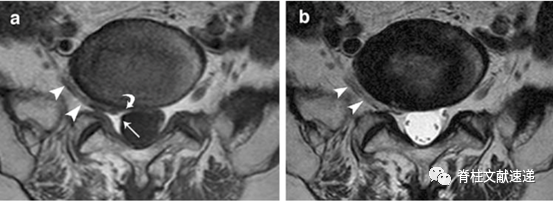

a.角形征(Corner sign):硬膜囊前外侧角的不对称形态;

b.新月形脂肪(Fat crescent sign):在异常神经根和硬膜之间存在月牙形硬膜外脂肪;

c.平行征(Parallel sign):异常神经根向椎间孔走形时可能非常平行于椎间盘,因此在椎间盘层面可见异常神经根的整个走形。

左图为定位像,右图为左图灰色区域的轴位像。可见三种征象的示意图。

三角所示为角形征,箭头所示为新月形脂肪。

箭头所示为角形征,弯箭头所示为新月形脂肪,双三角所示为平行征(即异常神经根影)。